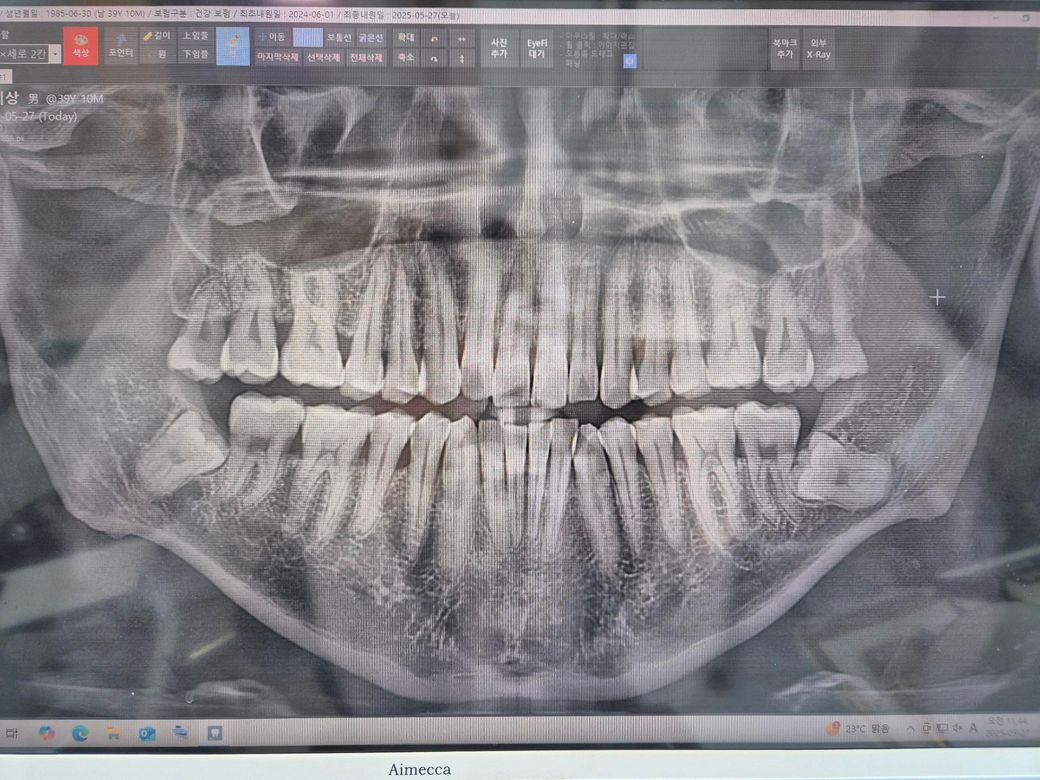

의사 선생님께서 잇몸치료도 매년해주시고 외관상이나 파노라마 상 큰 이상이 안보인다고 하십니다.

제 파노라마 상 어떤 문제가 보일까요?

• 1번 째 사진

엑스레이 상으로는 크게 문제가 잇어 보이진 않습니다. 일단은 치아가 예민해져서 그럴수 잇으니 약을 드시는게 좋을것같습니다 .

엑스레이상 특뱔히 이상한점 없습니다